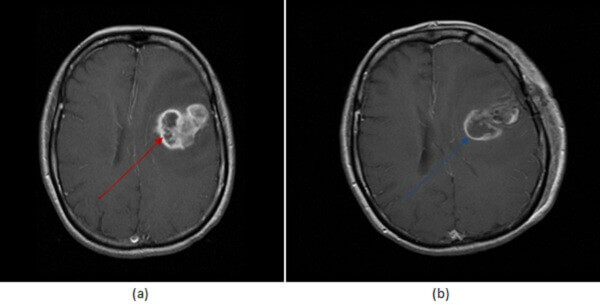

Diagnosis: Residual GBM after surgery

Figure 1: (a, red arrrow) Pre and immediate post operative (b, blue arrow) MRI imaging of a GBM demonstrates decreased but persistent enhancement within the surgical bed, consistent with recurrent tumor . Granulation tissue takes more than 48 hours to develop.

- Since granulation tissue takes more than 48 hours to form, mass like enhancement in the surgical bed in immediate post operative imaging is consistent with residual tumor.